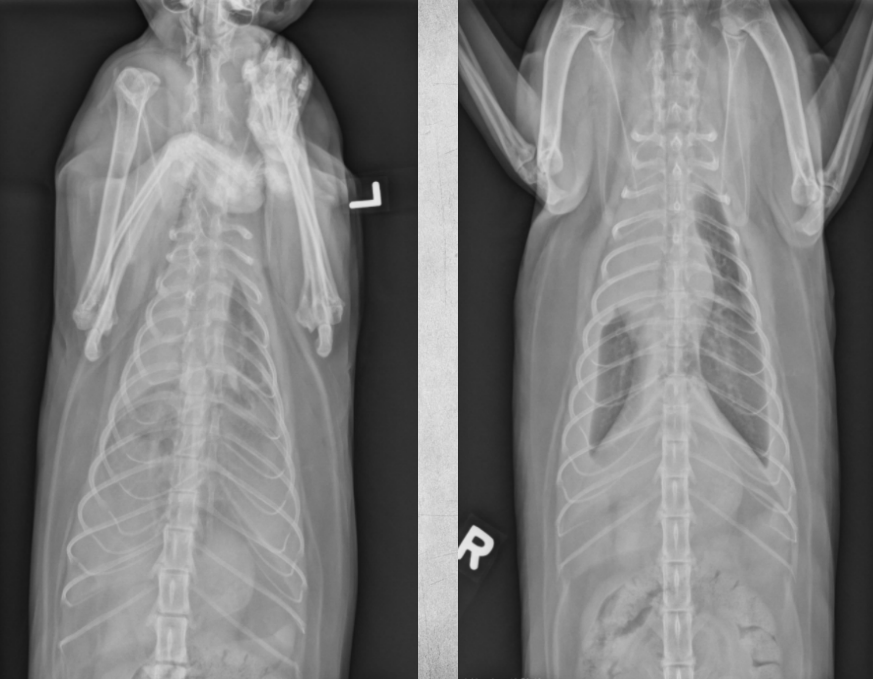

Main lung radiography patterns. (3)

● Alveolar

● Bronchial

● Interstitial

● 6 yo male cat

● Coughing

bronchial pattern

feline asthma